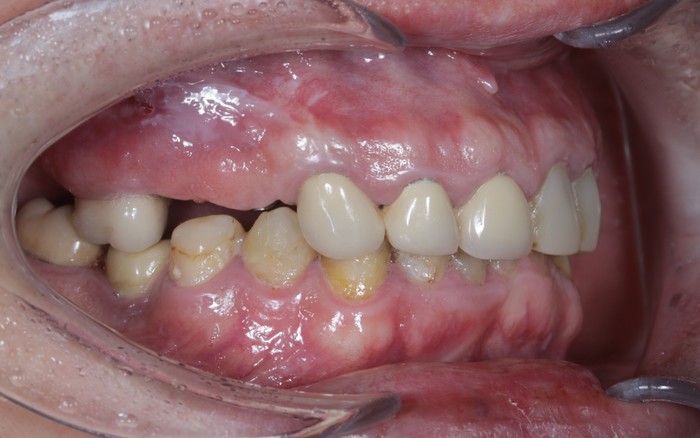

Вот пример того, когда пациент пренебрёг данным правилом:

Мужчине были установлены и спротезированы (временными коронками) имплантаты в другой клинике. После этого он пропал на несколько лет, не закончив полностью свое лечение. Явился лишь тогда, когда почувствовал «дискомфорт».

Кроме несостоятельности старых коронок и пломб, патологической стираемости зубов и т.д. - все эти годы сильно страдала гигиена.